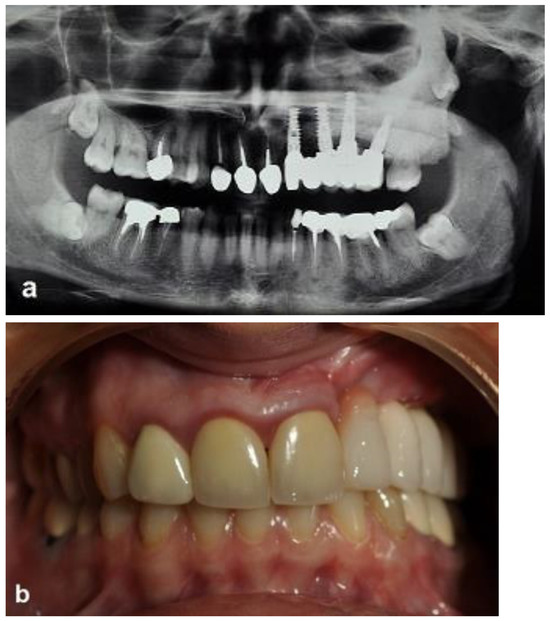

First surgery: Healing at the 4 weeks follow-up visit after the surgery was uneventful (Figure 5a,b). During dental implant placement surgery that was carried out six months after the first surgery, a good bone quality was observed with normal bleeding (Figure 6a). All implants were clinically and radiographically successfully osseointegrated when exposed 4 months later (Figure 7). The final rehabilitation after one year, and throughout the long period of the follow-up, provides satisfactory esthetic and functional outcomes (Figure 10a,b). There were no obvious changes in the lesion dimensions after 7 years (Figure 10c).

Figure 10. Clinical and radiographic images 7 years after the treatment show that there is no worsening of the FD lesion compared to the first picture that was obtained 7 years ago. (a) The CBCT view shows that the Bio-oss had been at least partially substituted by the FD lesion. (b) Intraoral view. (c) Extraoral views showing stable FD.